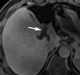

Salivary duct stricture

Salivary duct stricture (also termed salivary duct stenosis) is narrowing of the duct of a major salivary gland. Signs and symptoms Strictures are the second most common cause of chronic obstructive sialadenitis, after salivary stones. [Source: Wikipedia ]